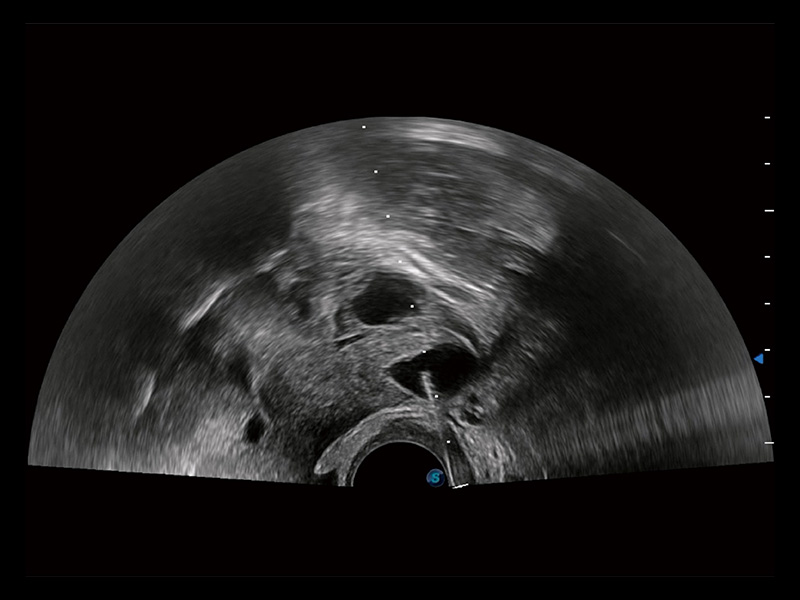

“生育问题”即关系民族复兴,也关系亿万家庭的幸福。随着婚育年龄推迟、社会压力增加等因素,越来越多人群也面临着“生不出、生不好”的问题。辅助生殖作为治疗不孕不育最有效的方法之一,也逐渐成为育儿新希望。而超声检查能为生殖需求人群的初诊评估提供宝贵的信息。 P20 Elite是玖鼎集团匠心打造的一款生殖应用型彩超。她继承玖鼎集团高端极光平台,突破性地将多款新型芯片及硬件模块进行整合,均衡了高端系统性能与小巧灵动机身。P20 Elite卓越的图像质量搭载专科探头,旨在为您提供全面的辅助生殖解决方案。

P20 Elite配备了丰富的生殖探头群和临床应用功能,在卵泡监测、穿刺取卵、胚胎移植、妊娠确认等领域,为生殖需求人群提供了新的临床机会,重新定义高端超声如何应用于生殖健康检查。